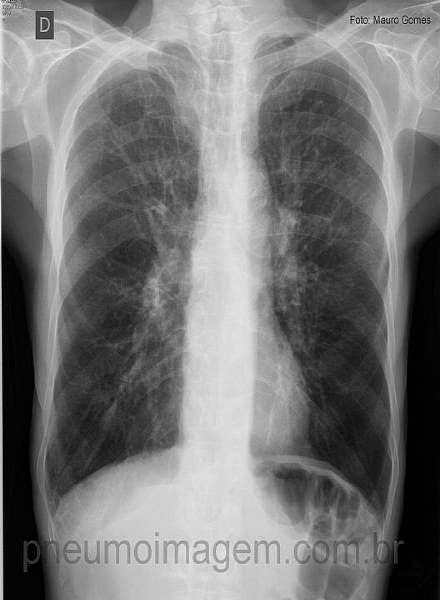

Veja o caso do mês de setembro do PneumoImagem, que trata sobre DPOC,

clicando aqui.